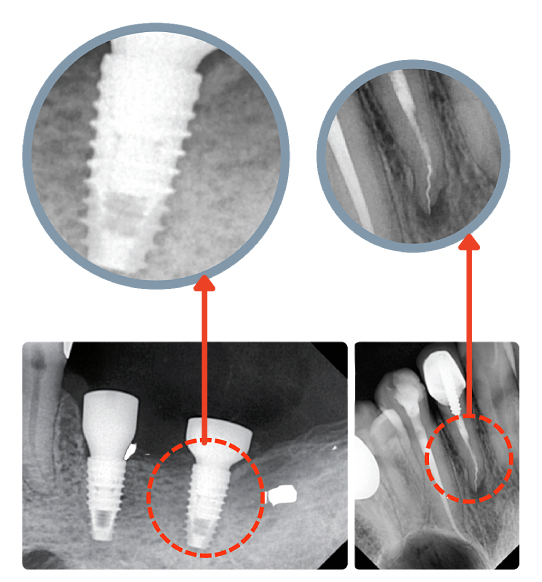

Благодаря высокой контрастности изображений врач легко различает ткани различной плотности и выявляет даже мелкие изменения — например, межзубные кариесы или периапикальные очаги воспаления.

Новые возможности визуализации: контрастные фильтры

EzSensor Classic оснащён набором предустановленных контрастных фильтров, которые помогают адаптировать изображение под конкретные задачи:

• Эндодонтия

• Терапевтическое лечение

• Реставрация

• Планирование имплантации

Благодаря этому врач может мгновенно настроить отображение структуры зуба и тканей, что повышает точность диагностики и качество коммуникации с пациентом.